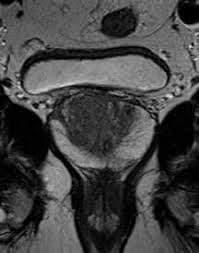

Discover the source of your pain with Sacroiliac MRI! Fast and reliable MRI imaging service with expert radiologists. Book your appointment now!